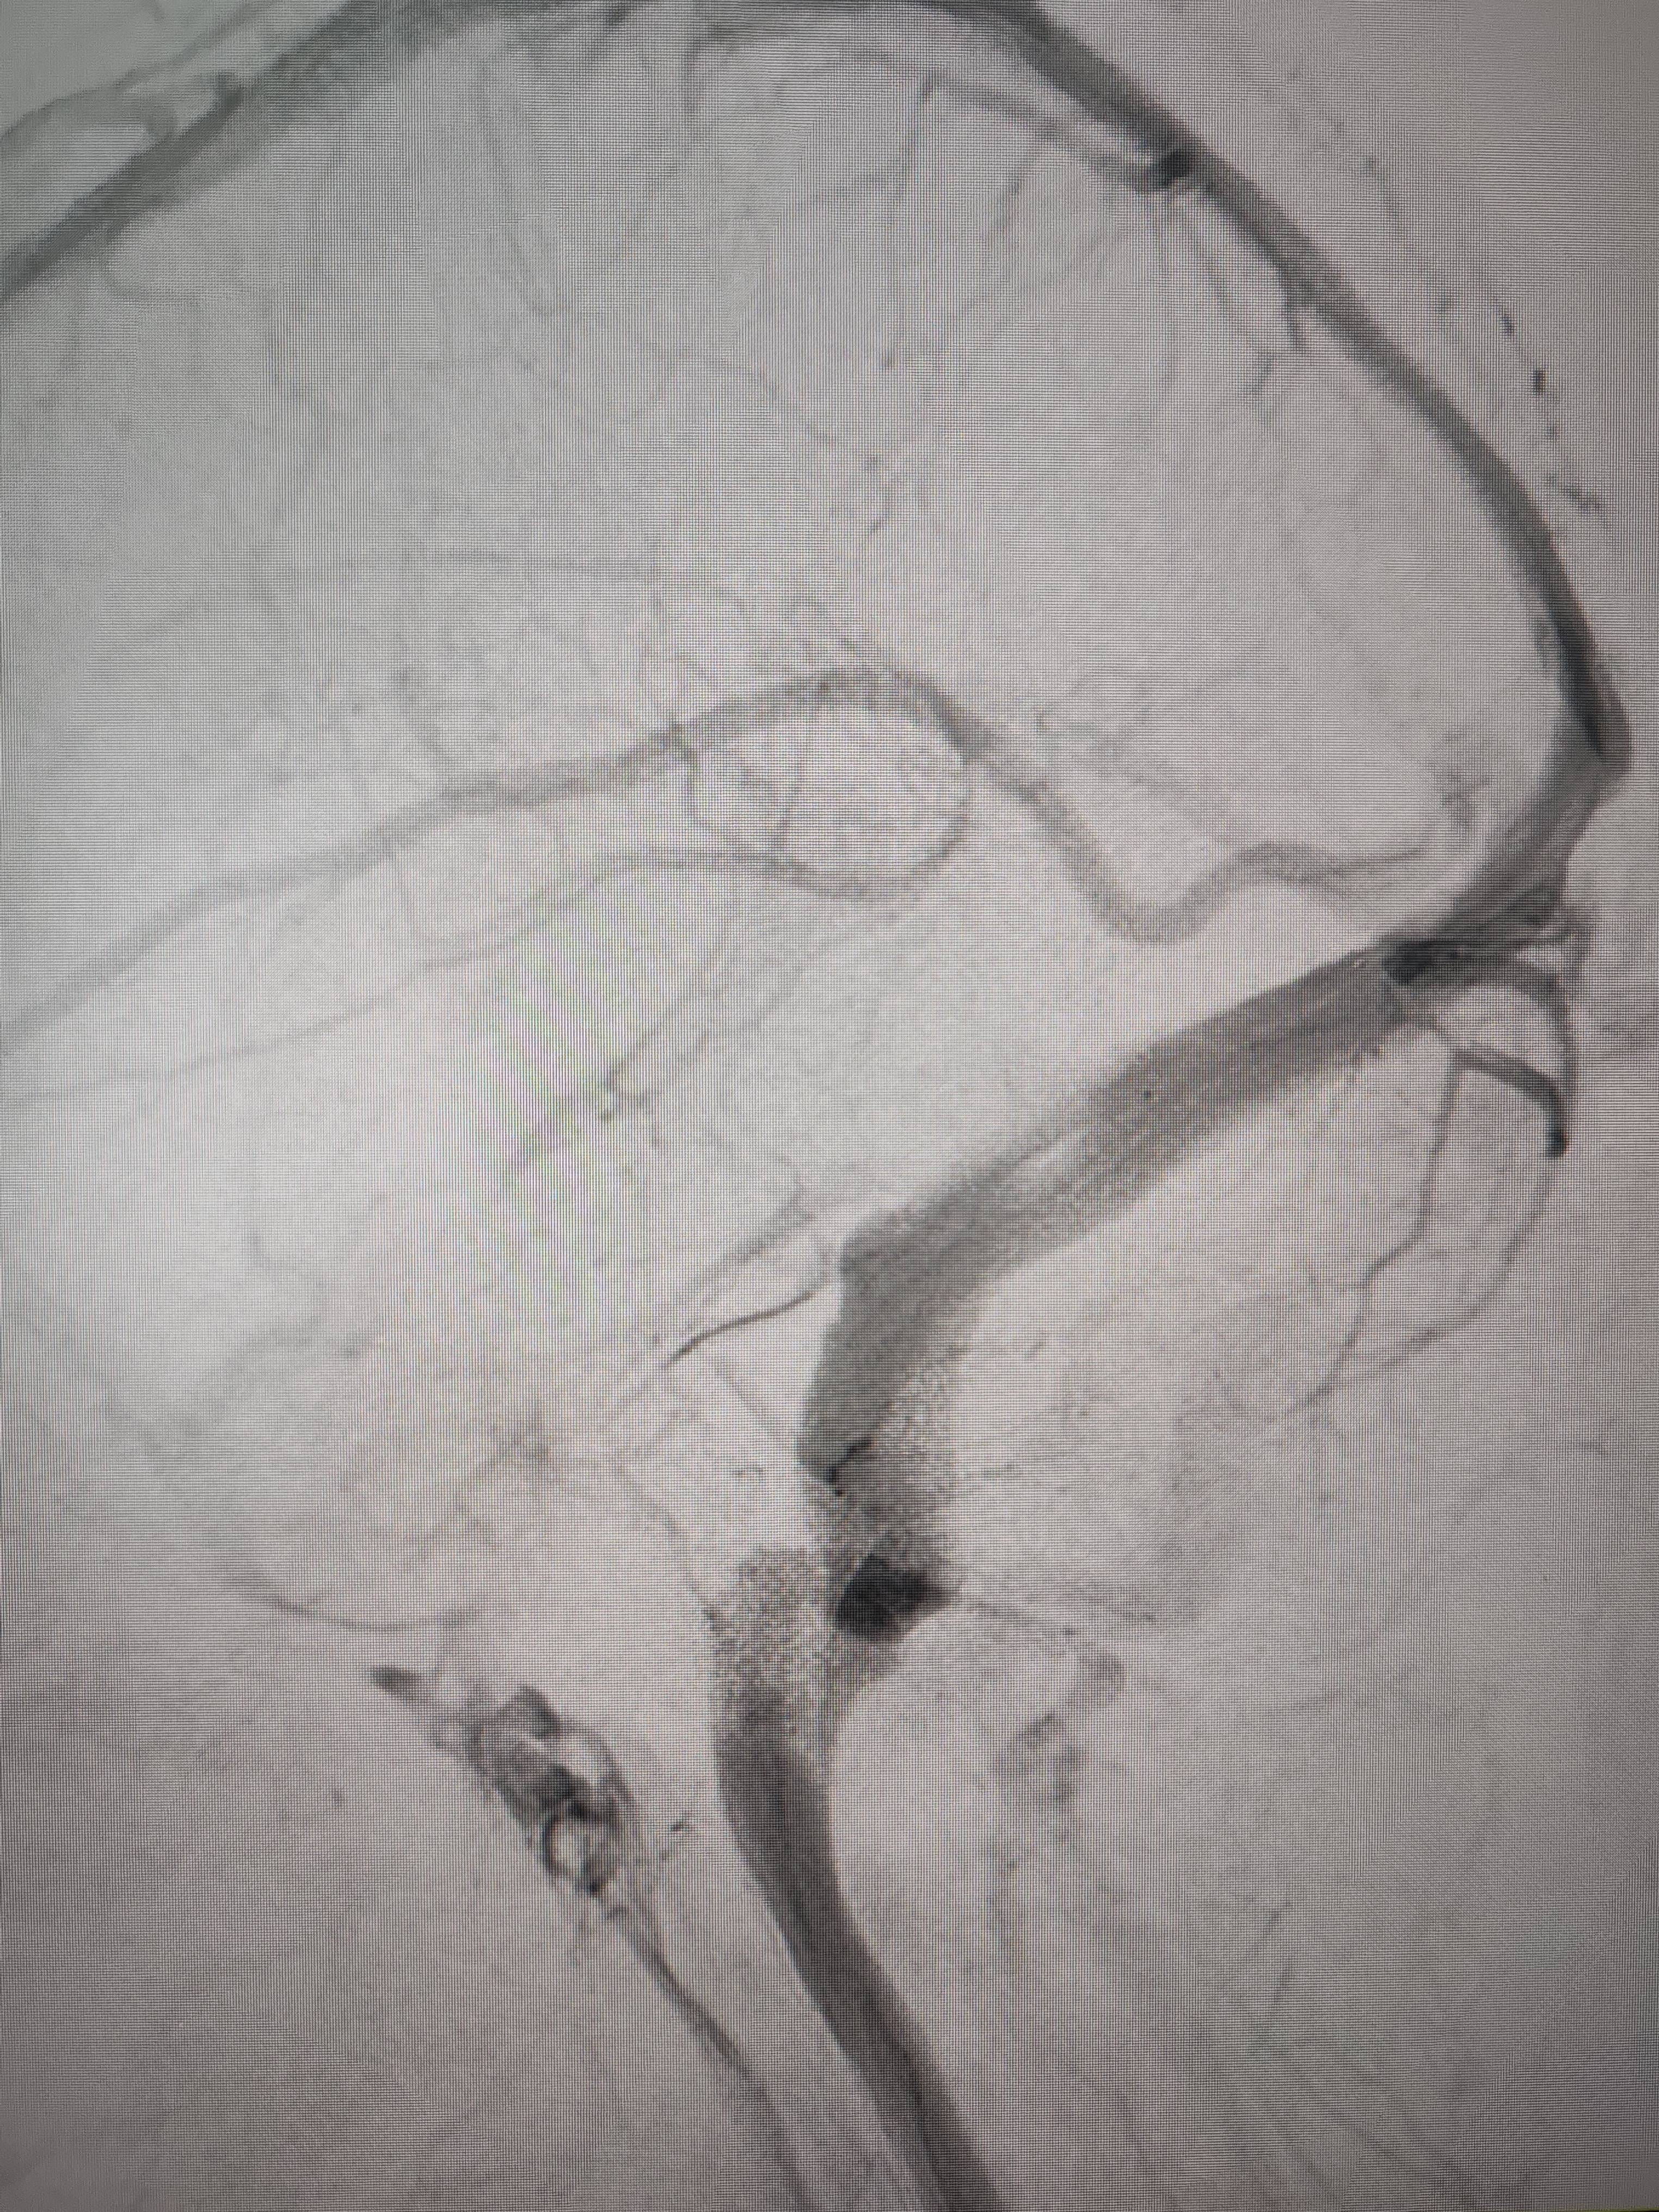

经过静脉窦支架置入手术治疗后,患者的静脉窦“堵点”被打通。 南方+ 欧阳少伟 拍摄

“从手术室出来,麻药清醒以后,我感觉整个世界都清静了,没想到效果这么立竿见影。”减轻病痛的赵女士,术后很是开心,次日就可下床自如活动,目前已康复出院。